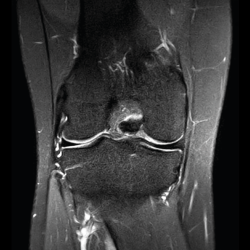

Resonancia magnética

Se basa en la propiedad que poseen los núcleos de hidrógeno de absorber energía electromagnética cuando están sometidos a un campo magnético intenso. La RM representa un mapa de la densidad de protones, o sea, de la distribución de agua por el organismo(12).

Se consiguen unas imágenes de alta resolución para la valoración de meniscos, ligamentos y tendones. Además, es especialmente útil en las rodillas operadas, lesiones tumorales, evaluación del cartílago y la visualización de los nervios(13).

1. Estudio de las estructuras intraarticulares

Es la prueba no invasiva de elección para valorar las lesiones internas de la rodilla(2). Aunque el estudio por RM es a menudo considerado como la prueba diagnóstica de elección para la detección de alteraciones meniscales, se asocia en ocasiones con errores diagnósticos(16).

1.1. Meniscos

Figura 30. Corte de secuencia sagital T2 Fat-Sat de resonancia magnética de rodilla: menisco externo normal.

Se identifican como estructuras hipointensas en todas las secuencias, con asta anterior y posterior de morfología triangular.

Figura 31. Corte de secuencia sagital T2 Fat-Sat de resonancia magnética de rodilla: menisco interno normal.

La RM es la técnica de elección en el diagnóstico de la patología meniscal(17)(Figuras 30, 31, 32, 33, 34 y 35).

Figura 32. Corte de secuencia coronal T2 Fat-Sat de resonancia magnética de rodilla: rotura de menisco interno horizontal.